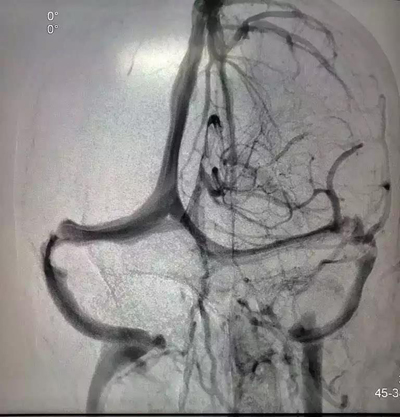

2018年12月4日,27岁的患者赵某某因视物模糊逐渐加重到医院检查治疗。经过眼底检查,发现患者双眼视乳头严重水肿。到底是什么原因引起患者视乳头出现水肿?腰穿提示患者颅内压增高,严重的颅内压增高可导致视乳头水肿、甚至脑疝,危及生命。头颅MRV、脑血管造影术等相关检查均提示右侧横窦血栓形成、狭窄可能,故给予抗凝、降颅压等治疗,但患者颅内压仍进行性增高,这意味着患者的视力会逐渐下降,甚至失明,患者及家属心急如焚。经医护人员认真讨论后认为,在抗凝等保守治疗效果欠佳的情况下,可进行颅内静脉窦支架植入术。但颅内静脉窦支架植入术难度高、风险大。为确保手术顺利完成,医院特邀首都医科大学附属天坛医院神经介入中心莫大鹏教授协助完成该手术。2019年1月5日下午,在全麻下为患者成功实施了颅内静脉窦支架植入术。术后造影显示患者右侧横窦狭窄消失,血流通畅,术后患者双眼憋胀感明显缓解,复查腰椎穿刺术,患者颅压降至正常,手术效果非常明显。